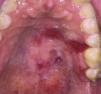

A middle-aged man complained of symptomatic oral lesions. Family history was positive for Fanconi anemia (FA). An intraoral examination revealed generalized erythroleukoplakia with focal ulcerations affecting the palate (Figure 1). Differential diagnosis included lichenoid lesions, dysplasia and squamous cell carcinoma (SCC). Previous biopsies demonstrated mild to moderate dysplasia. The patient underwent genetic testing and was diagnosed with FA.